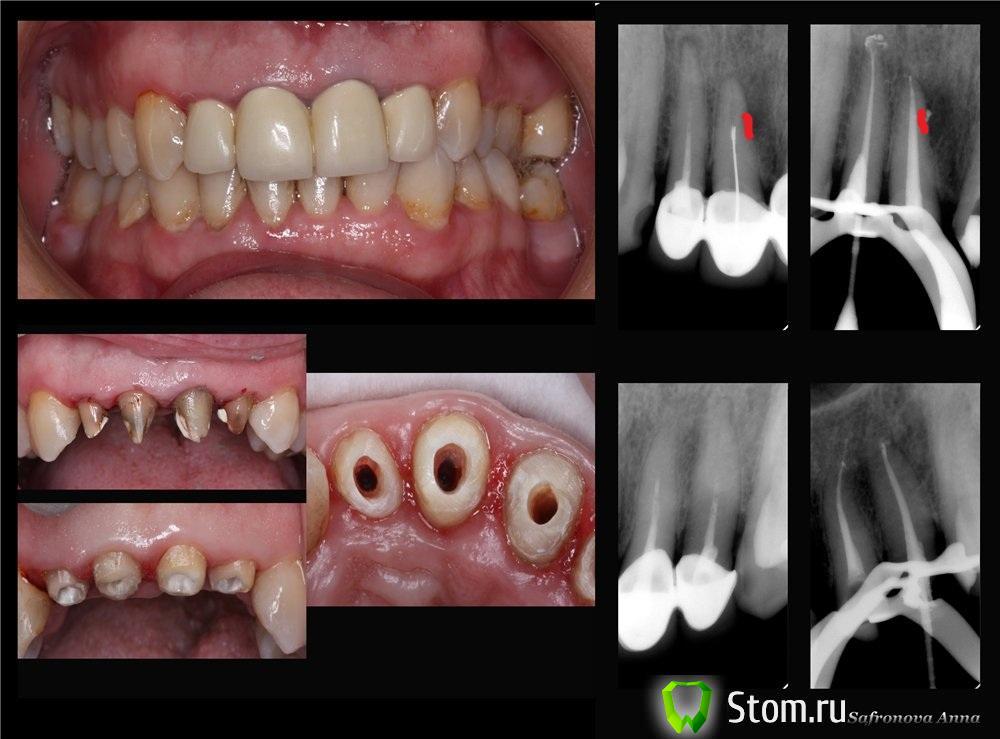

Demerchyan26 Опубликовано 2 декабря, 2011 Поделиться Опубликовано 2 декабря, 2011 Лично я бы сделал эндо, потом временные коронки из пластмассы, потом Rg контроль через 6 месяцев и если бы была положительная динамика то постоянную конструкцию.+К тому же по Rg просматривается кариес цемента на 11, и еще на 2-х мерном снимке нельзя увидеть реальные размеры поражения, а представьте что процесс распространился на небную часть корня, просто не просматривается на этом снимке, а вы поставили постоянную конструкцию. Как вы думаете, если зуб, не дай бог, уйдёт и пациент обратится в суд, кто будет прав (варианты с друзьями судьями не рассматривать)? Я работаю недавно, поэтому клинического опыта не имею и поэтому же стараюсь думать о самом плохом, что может произойти при протезировании. Ссылка на комментарий

kriokov Опубликовано 2 декабря, 2011 Поделиться Опубликовано 2 декабря, 2011 (изменено) +К тому же по Rg просматривается кариес цемента на 11, и еще на 2-х мерном снимке нельзя увидеть реальные размеры поражения, а представьте что процесс распространился на небную часть корня, просто не просматривается на этом снимке, а вы поставили постоянную конструкцию. Как вы думаете, если зуб, не дай бог, уйдёт и пациент обратится в суд, кто будет прав (варианты с друзьями судьями не рассматривать)? Я работаю недавно, поэтому клинического опыта не имею и поэтому же стараюсь думать о самом плохом, что может произойти при протезировании.кариеса цемента корня 11 не увидел на снимке. Думаю что нет разницы в тактике лечения в зависимости от того, с какой стороны от корня была деструкция кости, с небной или вестибулярной. Изменено 2 декабря, 2011 пользователем kriokov Ссылка на комментарий

Demerchyan26 Опубликовано 2 декабря, 2011 Поделиться Опубликовано 2 декабря, 2011 кариеса цемента 11 не увидел на снимке. Думаю что нет разницы в тактике лечения в зависимости от того, с какой стороны от корня была деструкция кости, с небной или вестибулярной.Граница корня нечеткая и неровная (в том месте где выведен материал на 11 зубе), причем и до и после лечения, поэтому предположил кариес корня. С какой стороны разницы нет, но объёмы деструкции имеет первостепенное значение. Извините, но я плохо рисую, но смысл в рисунке передал. Смысл в том, что часть кисты остается в тени корня и на снимке не отображается. Ссылка на комментарий

zybnaya feya Опубликовано 2 декабря, 2011 Автор Поделиться Опубликовано 2 декабря, 2011 (изменено) +К тому же по Rg просматривается кариес цемента на 11, и еще на 2-х мерном снимке нельзя увидеть реальные размеры поражения, а представьте что процесс распространился на небную часть корня, просто не просматривается на этом снимке, а вы поставили постоянную конструкцию. Как вы думаете, если зуб, не дай бог, уйдёт и пациент обратится в суд, кто будет прав (варианты с друзьями судьями не рассматривать)? Я работаю недавно, поэтому клинического опыта не имею и поэтому же стараюсь думать о самом плохом, что может произойти при протезировании. В каком месте вы "кариес цемента" увидели? покажите стрелочкой,пожалуйста. Прежде чем ставить постоянную конструкцию,я перелечила каналы и дельты запечатала( деструкция по причине их наличия образовалась)Не важно на какой поверхности очаг деструкции. Сходите на лекции по эндопаропоражениям,многое станет на свои маста Изменено 2 декабря, 2011 пользователем zybnaya feya Ссылка на комментарий

Demerchyan26 Опубликовано 2 декабря, 2011 Поделиться Опубликовано 2 декабря, 2011 В каком месте вы "кариес цемента" увидели? покажите стрелочкой,пожалуйста. Прежде чем ставить постоянную конструкцию,я перелечила каналы и дельты запечатала( деструкция по причине их наличия образовалась)Не важно на какой поверхности очаг деструкции. Сходите на лекции по эндопаропоражениям,многое станет на свои маста Я вам не говорю о локализации деструкции, я говорю о размере деструкции и то что на 2-х мерном снимке не всегда видны действительный объем деструкции. Ссылка на комментарий

kriokov Опубликовано 2 декабря, 2011 Поделиться Опубликовано 2 декабря, 2011 (изменено) Граница корня нечеткая и неровная (в том месте где выведен материал на 11 зубе), причем и до и после лечения, поэтому предположил кариес корня. С какой стороны разницы нет, но объёмы деструкции имеет первостепенное значение. Извините, но я плохо рисую, но смысл в рисунке передал. Смысл в том, что часть кисты остается в тени корня и на снимке не отображается.понятно все о чем Вы говорите и по рисунку и без. 1. Думаю ни кто не скажет сказать по снимку, киста это, или нет со 100%2. Оставшейся поддерживающей зуб костной структуры достаточно, раз он не подвижен3. Лечение в данном случае исчерпывающее на момент обращения - полноценная эндодонтия, т.е закрытие ворот для реконтаминации микр флоры ч\з канал. Карманов нет, - откуда взяться сомнительному прогнозу? Изменено 2 декабря, 2011 пользователем kriokov Ссылка на комментарий

kriokov Опубликовано 2 декабря, 2011 Поделиться Опубликовано 2 декабря, 2011 То есть вы считаете, что эти изменения не являются дополнительным риском для возникновений осложнений (при качественном эндо)?Рентгенологически 2д действительно трудно иногда определиться с обьемом деструкции в обл корня, видимо поэтому и оценивается функциональный прогноз по совокупности данных всех исследований- перкуссия, подвижность, наличие или отсутствие свища, пародонтальная симптоматика и т.д В данном случае : деструкция есть - до лечения, зуб неподвижен, свища нет, карманов нет.Насчет цемента корня- помоему он разный бывает клеточный и бесклеточный и еще какой то, и имеет свойство регенерировать если устранен повреждающий агент. Правда, деструкции цемента на корне 11 не вижу. Ссылка на комментарий